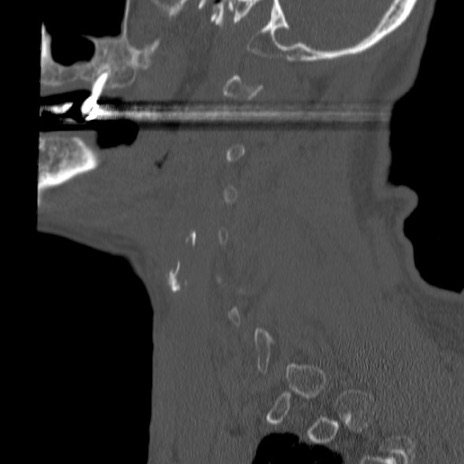

症例46 頚椎CT(矢状断像)

【症例】80歳代男性

【主訴】両側頚部〜上肢のしびれ

【現病歴】昨日、自宅内で転倒、その後より上記症状あり。意識障害なし。

【身体所見】両側上肢のallodynia(熱痛覚過敏)あり。MMTおよびDTRは正確な所見取れず。両上肢の挙上はなんとか可能。

異常所見と診断は?